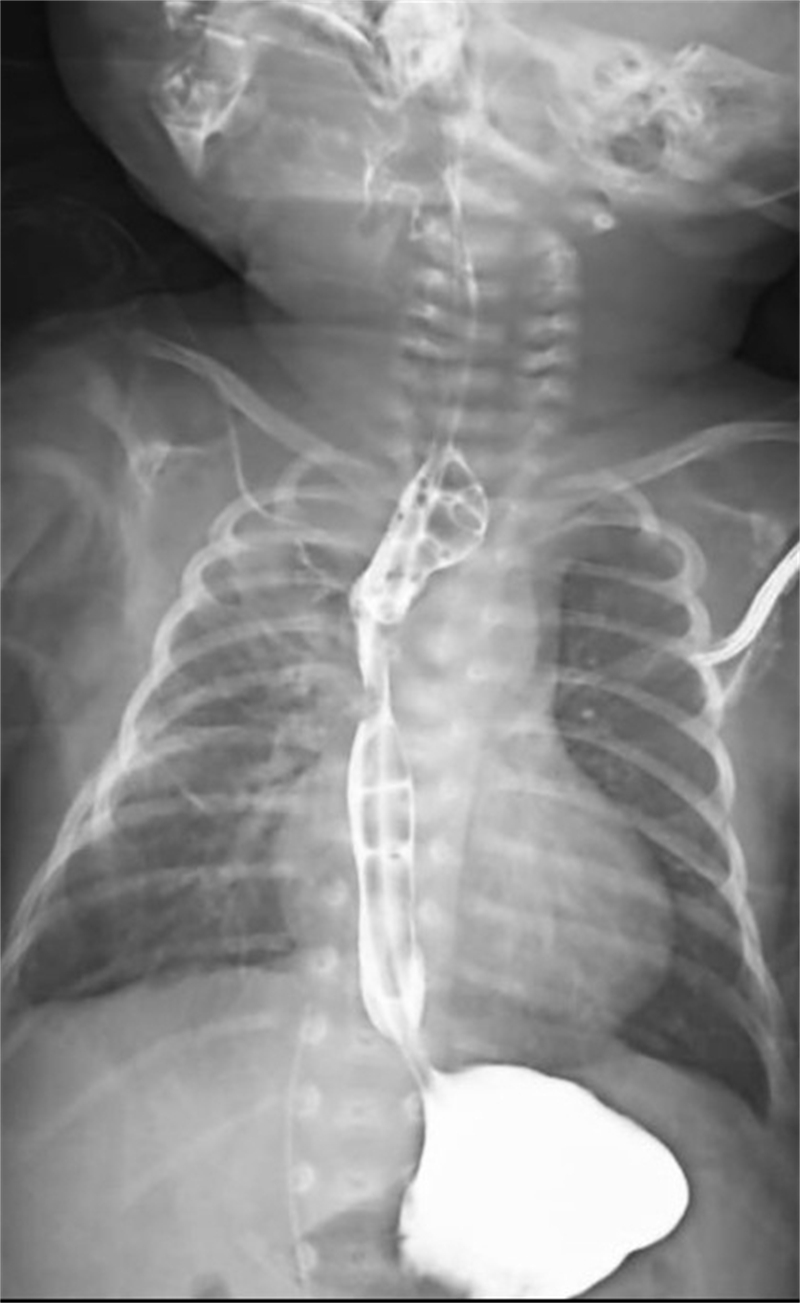

面對這一突發情況,經驗豐富的新生兒科醫生立即警覺:萱萱有可能患有少見且嚴重的新生兒先天性疾病——食管閉鎖。為了盡快明確診斷,新生兒科與小兒外科討論后,緊急聯系放射科為萱萱安排了消化道造影、CT掃描等全面檢查。最終,檢查結果明確診斷:先天性食管閉鎖Ⅲ型伴食管氣管瘺。

術后僅1天,萱萱便能通過留置胃管接受腸內營養支持。在新生兒科醫護人員的精心照料下,術后3周復查消化道造影顯示手術切口愈合良好,萱萱終于可以自己吃奶啦!